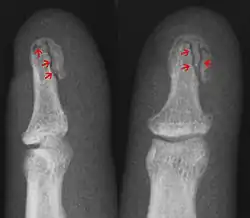

| Avulsion fracture | A fragment of bone is separated from the main mass (image shows a Busch fracture) | |||